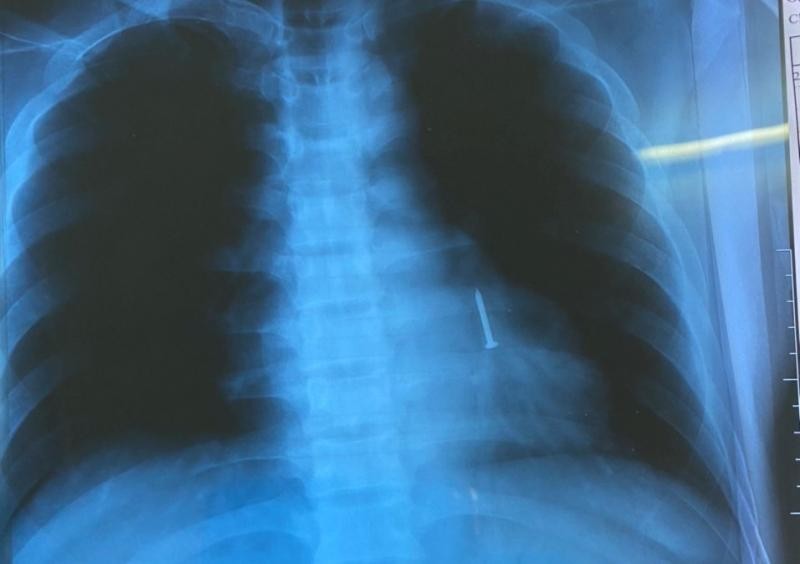

(Ngày Nay) - Tối 28/2, các bác sĩ khoa Nội hô hấp - Miễn dịch dị ứng, Bệnh viện Đà Nẵng đã nội soi gắp thành công cây đinh sắt dài 3cm nằm trong phế quản cho một bệnh nhân làm nghề thợ hồ.

Ngày 22/2, trong quá trình làm việc, ông ngậm sẵn 3 cây đinh trong miệng để tiện đóng cốp pha nhưng do vô tình nói chuyện khiến đinh hóc vào phổi. Sau khi bị hóc, bệnh nhân cảm giác hơi vướng nhưng không khó thở, chỉ ho một cơn gọi là hội chứng xâm nhập.

Bệnh nhân có đi khám tại địa phương, được khuyên về theo dõi tìm đinh trong phân. Nhưng sau 4 ngày không thấy đinh nên bệnh nhân quyết định nhập cấp cứu bệnh viện Đà Nẵng và được chỉ định nhập khoa Nội hô hấp - Miễn dịch dị ứng.

Sau khi khai thác bệnh sử, thực hiện các kỹ thuật cận lâm sàng, kíp bác sĩ khoa Nội hô hấp - Miễn dịch dị ứng đã nội soi phế quản, gắp đinh sắt dài 3cm nằm trong phổi trái của bệnh nhân sau 30 phút. Hiện tại, sức khỏe bệnh nhân đã ổn định và chuẩn bị ra viện.

Bác sĩ Hoàng Thị Tâm, Phó trưởng khoa Nội hô hấp - Miễn dịch dị ứng chia sẻ: “Đây là trường hợp bệnh nhân bị hóc dị vật có kích thước khá lớn, nhọn. Hơn nữa đinh ở vị trí sâu, đầu đinh hướng phía trên, trơn nên gây nhiều khó khăn, phải sử dụng dụng cụ chuyên mới lấy được”.